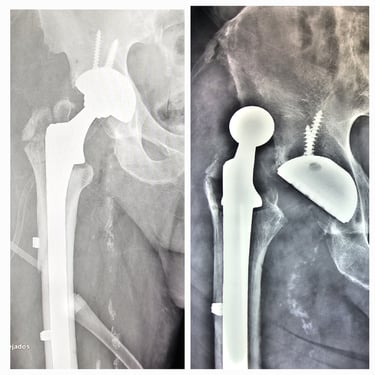

Artroplastia de cadera (prótesis total/parcial).

Cirugía de revisión de cadera y rodilla.

Manejo de secuelas y complicaciones de prótesis de cadera y rodilla.